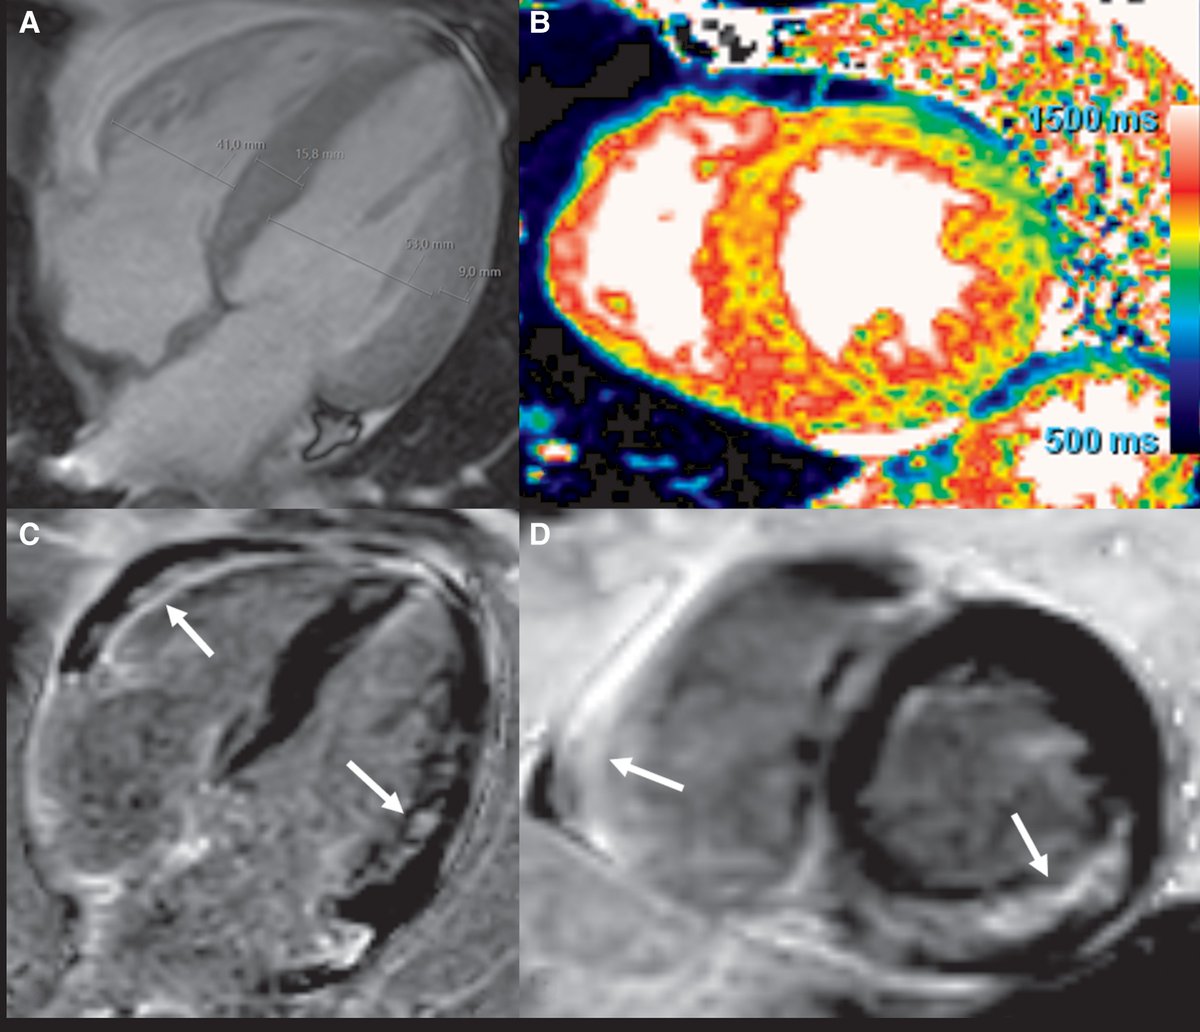

#JADEL Are you familiar with "TUSI-Valves"? doi.org/10.1016/j.case… Important CASE series now in @CASEfromASE - TUSI (Pink cocaine "cocktail" - ecstasy common) - Non-infective / Non-rheumatic VHD - Fibroblast hyperactivity - Echo = thick, restricted leaflets @ASE360